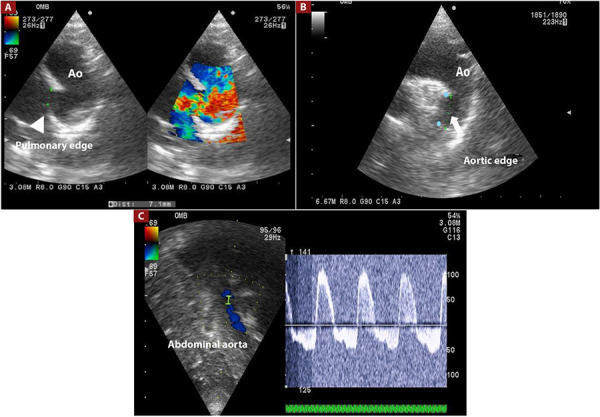

Objetive: Percutaneous occlusion of patent ductus arteriosus (PDA) has classically been performed entirely by fluoroscopy, however in recent years, transthoracic echocardiography (TE) has been used as an aid to fluoroscopy or entirely by echocardiography, which avoids access of femoral artery, use of contrast and decrease in time and dose of radiation exposure. The objective of this study was to evaluate the success rate with the use of TE in percutaneous PDA closure.

Material and method: Descriptive, comparative, retrospective study between patients in whom PDA closure was performed with fluoroscopy plus angiography (group 1) and fluoroscopy plus ET (group 2), between January 2018 and December 2022. The data were obtained from the clinical history electronic and procedure report.

Results: One hundred eight patients were analyzed, fluoroscopy group (n: 57) and TE (n: 51). The success rate in PDA occlusion using TE was 100% and 98% for the fluoroscopy group, with no statistically significant difference The average age of group 2 was 2.9 years, while the average age of group 1 was 5 years (p=0.001), the average fluoroscopy time in group 1 was 16.9 min and 4.71 min in group 2 (p < 0.001); the fluoroscopy dose in group 1 was 68.98 mGy and 5.17 mGy in group 2 (p<0.001). Krichenko, but without significant difference in both groups.

Conclusions: The success rate of percutaneous PDA closure using echocardiography and fluoroscopy is appropiate, with a success rate similar to the classic technique. In addition, it makes it possible to reduce the dose and time of fluoroscopy, avoid the use of contrast, and access the femoral artery.